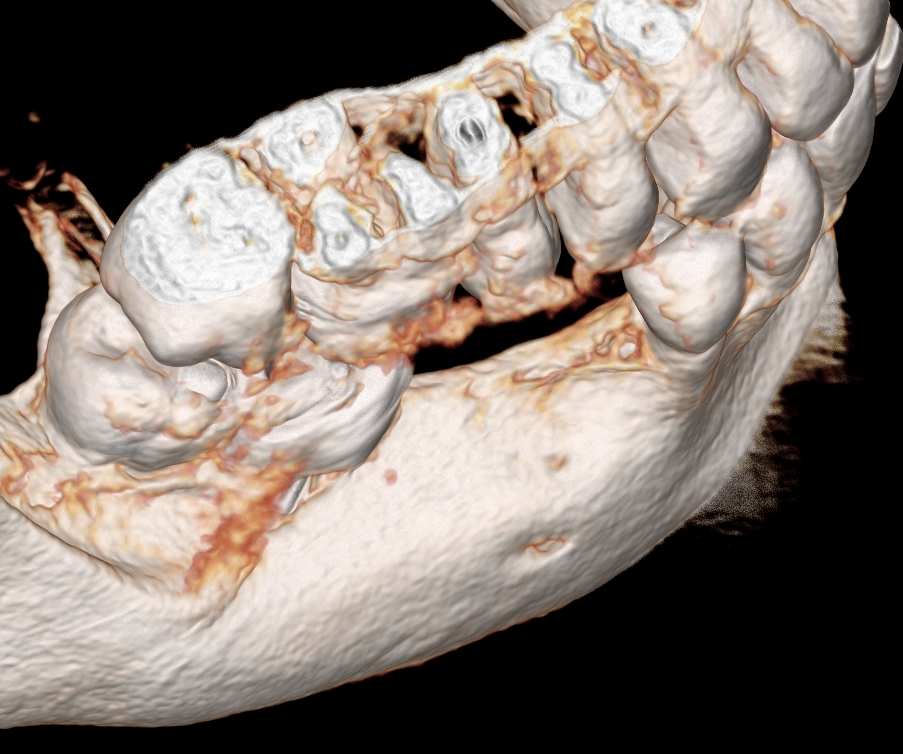

Ryc. 2. Szerokość wyrostka. Ryc.  3. Deficyt objętościowy masy kostnej i zanik blaszki przedsionkowe.

Ryc. 4. Rekonstrukcja 3d-wyjsciowy kształt wyrostka.